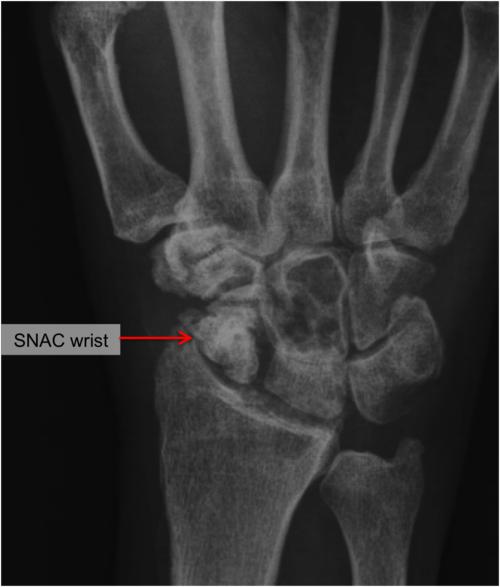

对于陈旧性舟状骨骨折或骨不连者,往往需要切开复位,植骨,再行内固定术,延长了治疗时间。舟状骨骨折如果没有得到正确的治疗,甚至会导致舟状骨坏死,引起舟状骨变形,塌陷,导致腕关节炎,引起严重的腕关节痛,活动范围下降。所以对于舟状骨骨折应该给予足够重视,腕关节外伤后反复疼痛,及时X线检查,甚至CT检查明确诊断,避免漏诊,早期积极干预,避免遗留后遗症。

引用Dr. Schreiber图片,舟状骨坏死导致腕关节炎